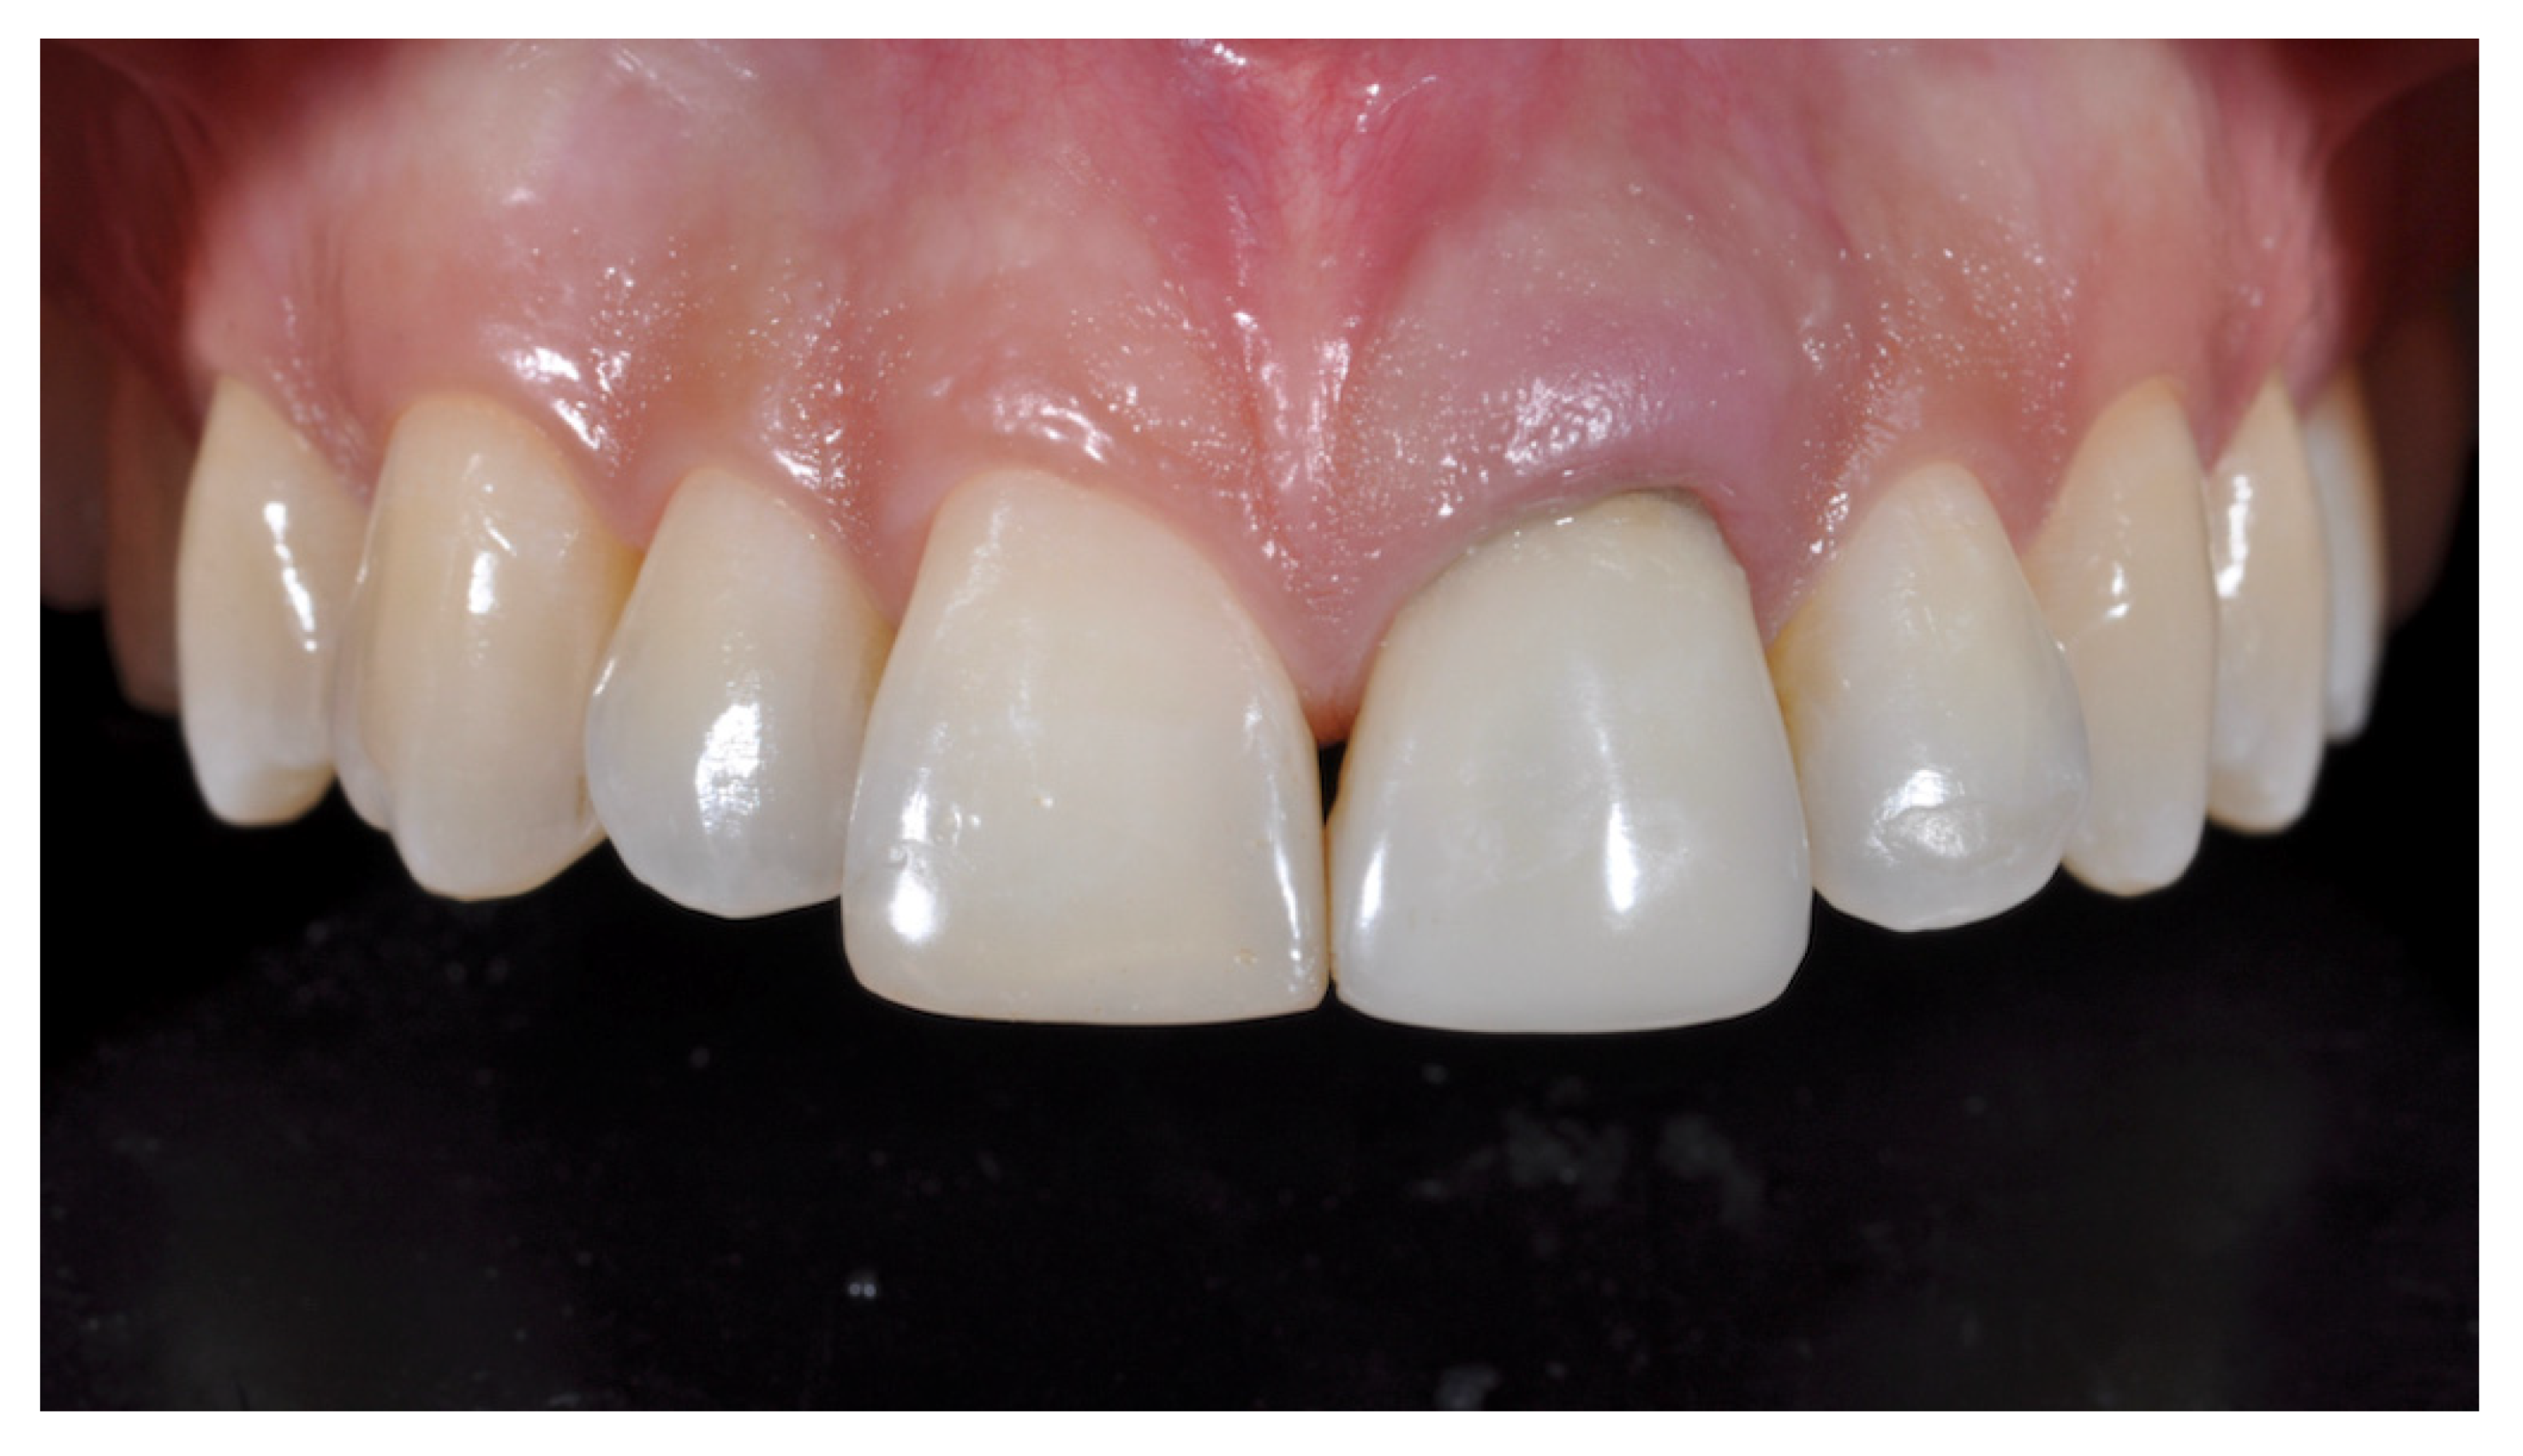

2. Case Presentation